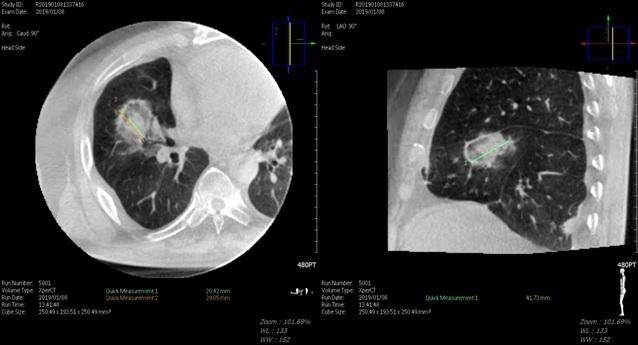

폐암 치료를 위한 고주파 열 치료술은 컴퓨터단층촬영(CT)ㆍ초음파검사 등 영상 의학 장비 유도 하에 시술 기구를 안전한 경로로 폐 내부 병변에 넣은 뒤 열을 발생해 종양을 치료하는 기법이다.

연구팀은 다학제 진료로 결정된 폐 전이 대장암 31명의 환자를 대상으로 시행된 48회의 폐 고주파 열 치료술을 분석했다.

대부분의 환자는 2박 3일 단기 입원을 해 국소마취로 시술을 받았다. 치료 성적은 1년과 2년차 국소 무재발 생존율이 각각 81%와 64%였고 전체 생존율은 각각 98%와 97%였다. 특히 3D 단층 영상을 재구성하는 방법으로 Cone-beam CT로 표적을 정확히 표적해 90%의 고주파 열 치료술 성공률을 기록했다. 18% 정도에서 시술 후 기흉이 발생하는 합병증이 있었지만, 임상적으로 큰 문제가 되는 경우는 없었다.